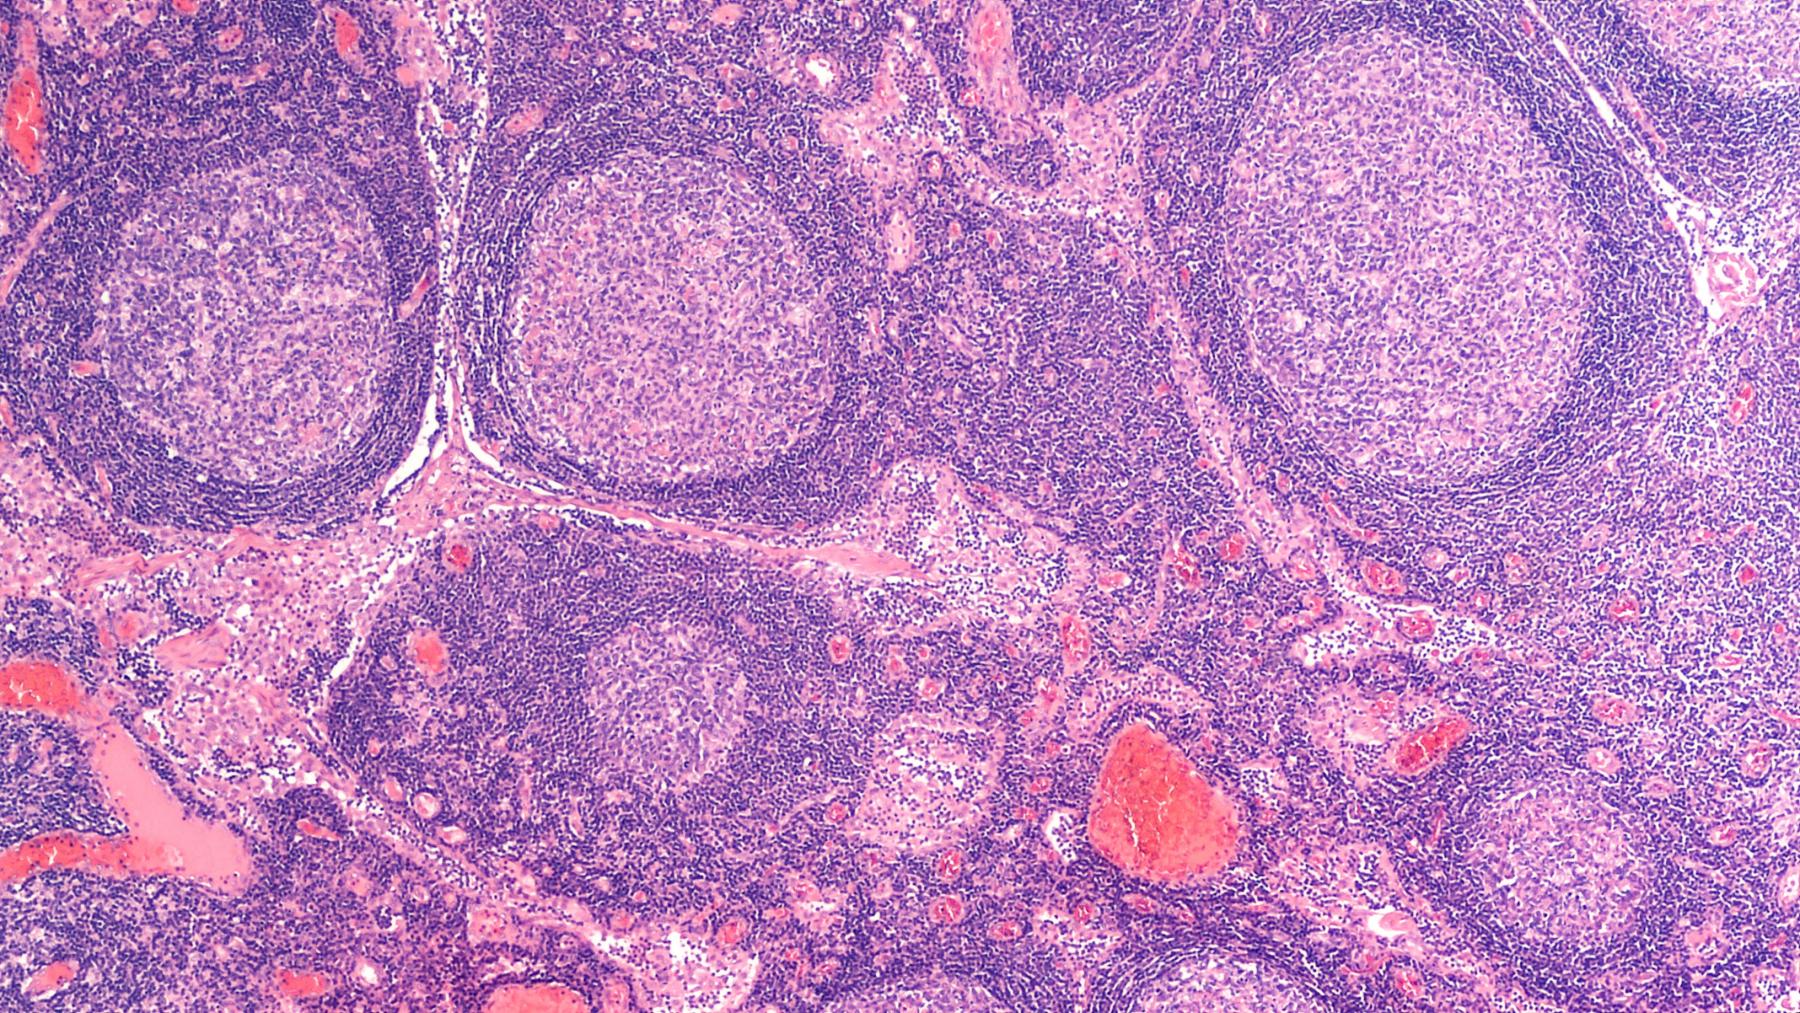

Лимфатические узлы представляют собой важнейшую часть периферической иммунной системы. В организме их насчитывается более 500, они объединены в группы и сопровождают лимфатические сосуды, по которым лимфа оттекает из различных органов. Каждый из лимфоузлов состоит из нескольких функциональных зон:

лимфоидных узелков, представленных В-клетками;

паракортикальной зоны, где находятся Т-лимфоциты, проходящие антиген-зависимую дифференцировку;

мозгового вещества, в которое мигрируют B-лимфоциты и где они дифференцируются в плазматические клетки-продуценты иммуноглобулинов (антител).